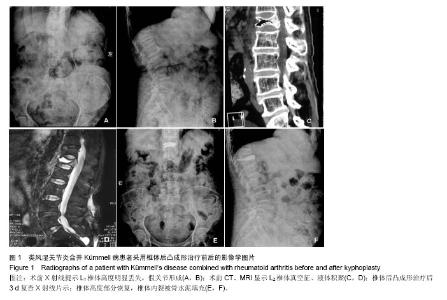

Bone cement kyphoplasty for repair of rheumatoid arthritis combined with Kümmell’s disease: a follow-up addressing vertebral height and spinal stabilization

METHODS: From June 2012 to July 2013, 11 female patients at the age of 65.4±5.1 years with Kümmell’s disease combined with rheumatoid arthritis, who suffered from severe back pain, were treated with bone cement vertebroplasty. Back pain and imaging indexes were compared and observed before surgery and during follow-up. Imaging indexes contained preoperative and postoperative anterior height of vertebral body after fractures, the ratio of anterior height to posterior height of the vertebral body, and local kyphosis angle (Cobb method).

RESULTS AND CONCLUSION: No patients were lost to follow up. 11 patients were followed up for 6 to 12 months. Significant differences in follow-up and preoperative Visual Analogue Scale scores, anterior height of vertebral body after fractures, the ratio of anterior height to posterior height of the vertebral body, and local kyphosis angle were detected (P < 0.05). Two patients experienced bone cement leakage. No severe complications appeared such as pulmonary embolism or neurological dysfunction. These data confirmed that bone cement vertebroplasty for rheumatoid arthritis combined with Kümmell’s disease can effectively lessen back pain, partially restore the height of vertebral body after fracture, rebuild spinal stabilization, reduce local kyphosis, and is a safe effective repair method.